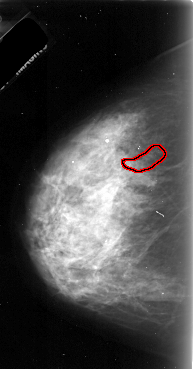

FILE: A_1072_1.LEFT_CC.OVERLAY

TOTAL_ABNORMALITIES 1

ABNORMALITY 1

LESION_TYPE CALCIFICATION TYPE PLEOMORPHIC DISTRIBUTION LINEAR

ASSESSMENT 4

SUBTLETY 2

PATHOLOGY MALIGNANT

TOTAL_OUTLINES 1

BOUNDARY